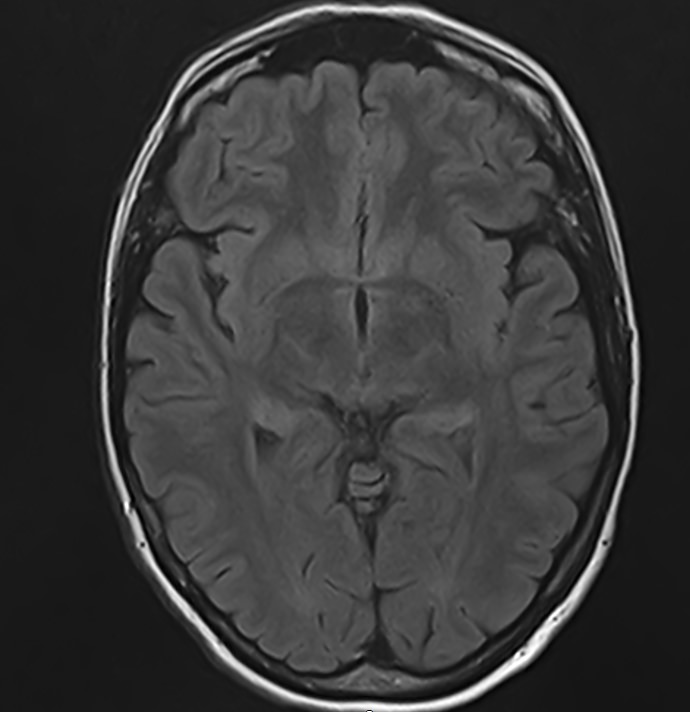

Для диагностики поражения черепно-мозговых нервов, а также оценки состояния окружающих их тканей и визуализации сосудистой сети головного мозга в клинике «Доступная медицина» проводится комплексное обследование МРТ головного мозга + Мр-ангиография головного мозга + МР-венография головного мозга + черепно-мозговые нервы. Данное обследование включает в себя несколько протоколов: стандартный – для оценки состояния всех структур головного мозга и дополнительные – для изучения очагов поражения черепных нервов и визуализации всей сосудистой системы головного мозга.

Исследования выполняются на современном высокопольном томографе экспертного класса TOSHIBA VANTAGE TITAN 1,5 Тесла, который использует разные режимы сканирования с толщиной среза от 1мм в различных плоскостях с последующей цифровой обработкой полученных данных для создания трехмерных изображений. МР-ангиография отображает состояние артериальной системы кровоснабжения головного мозга. МР-венография головного мозга позволяет детально изучить особенности венозного русла головного мозга.

Компьютерная программа обрабатывает данные, полученные при сканировании, и формирует объемные изображения как самого мозга, так и сосудистой системы в отдельности без прилегающих тканей. Методики применяются одновременно и взаимодополняют друг друга.